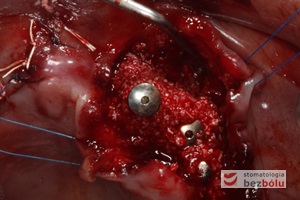

Implanty in situ - wprowadzone podwyrostkowo implanty i wyrostek zębodołowy przygotowany do augmentacji

Implanty in situ – wprowadzone podwyrostkowo implanty i wyrostek zębodołowy przygotowany do augmentacji

Uzupełnienie ubytków śródkostnych - substytut kości zmieszany z krwią pacjenta i wiórami kostnymi wypełnia deficyty kostne

Uzupełnienie ubytków śródkostnych – substytut kości zmieszany z krwią pacjenta i wiórami kostnymi wypełnia deficyty kostne